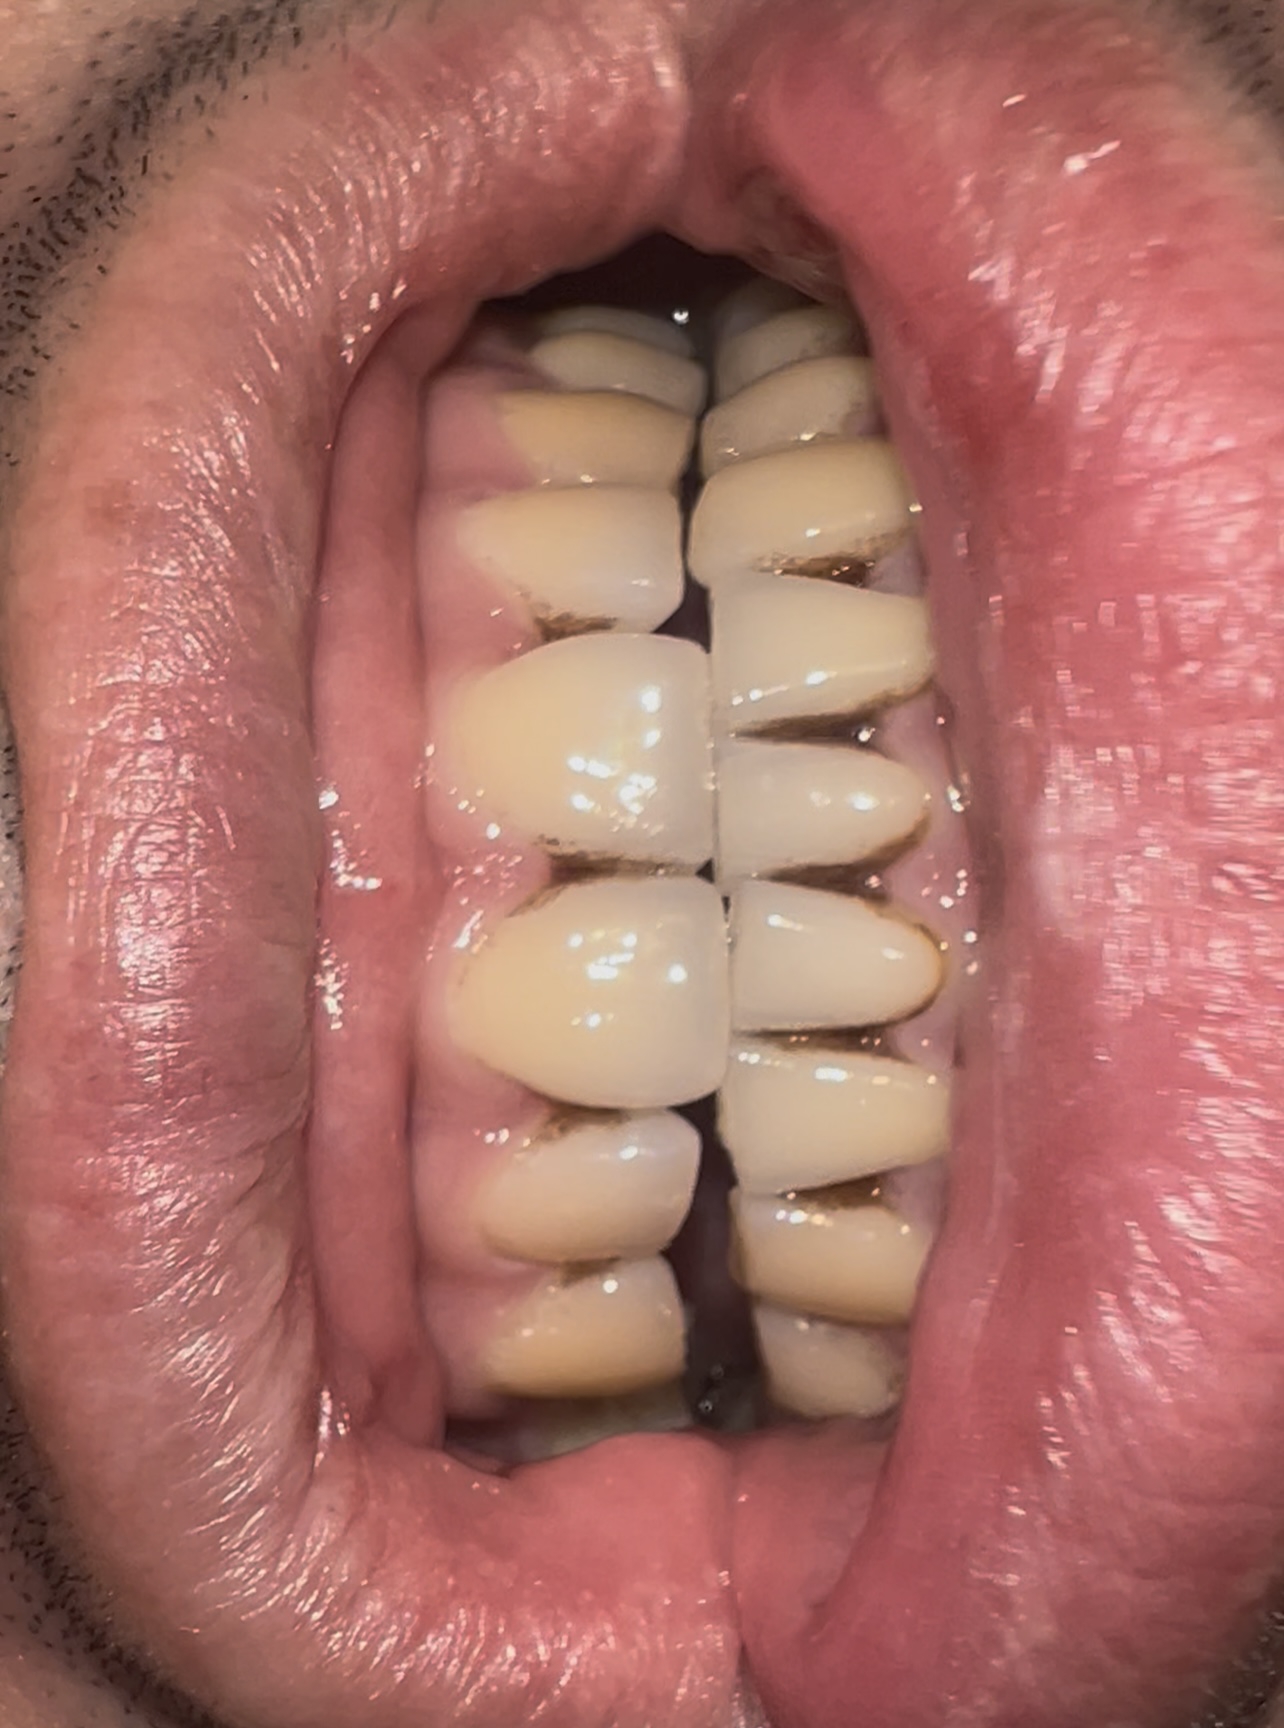

У меня глубокий прикус, нижняя челюсь сильно западает под верхнюю, если сделать ей смыкание по передним зубам, то не смыкаются жевательные зубы. И что делают в таком случае? Как вытянуть жевательные зубы, чтобы они сомкнулись? Или зубы наращивают пломбами?

Аноним 24/07/25 Чтв 03:52:58 1633058 14